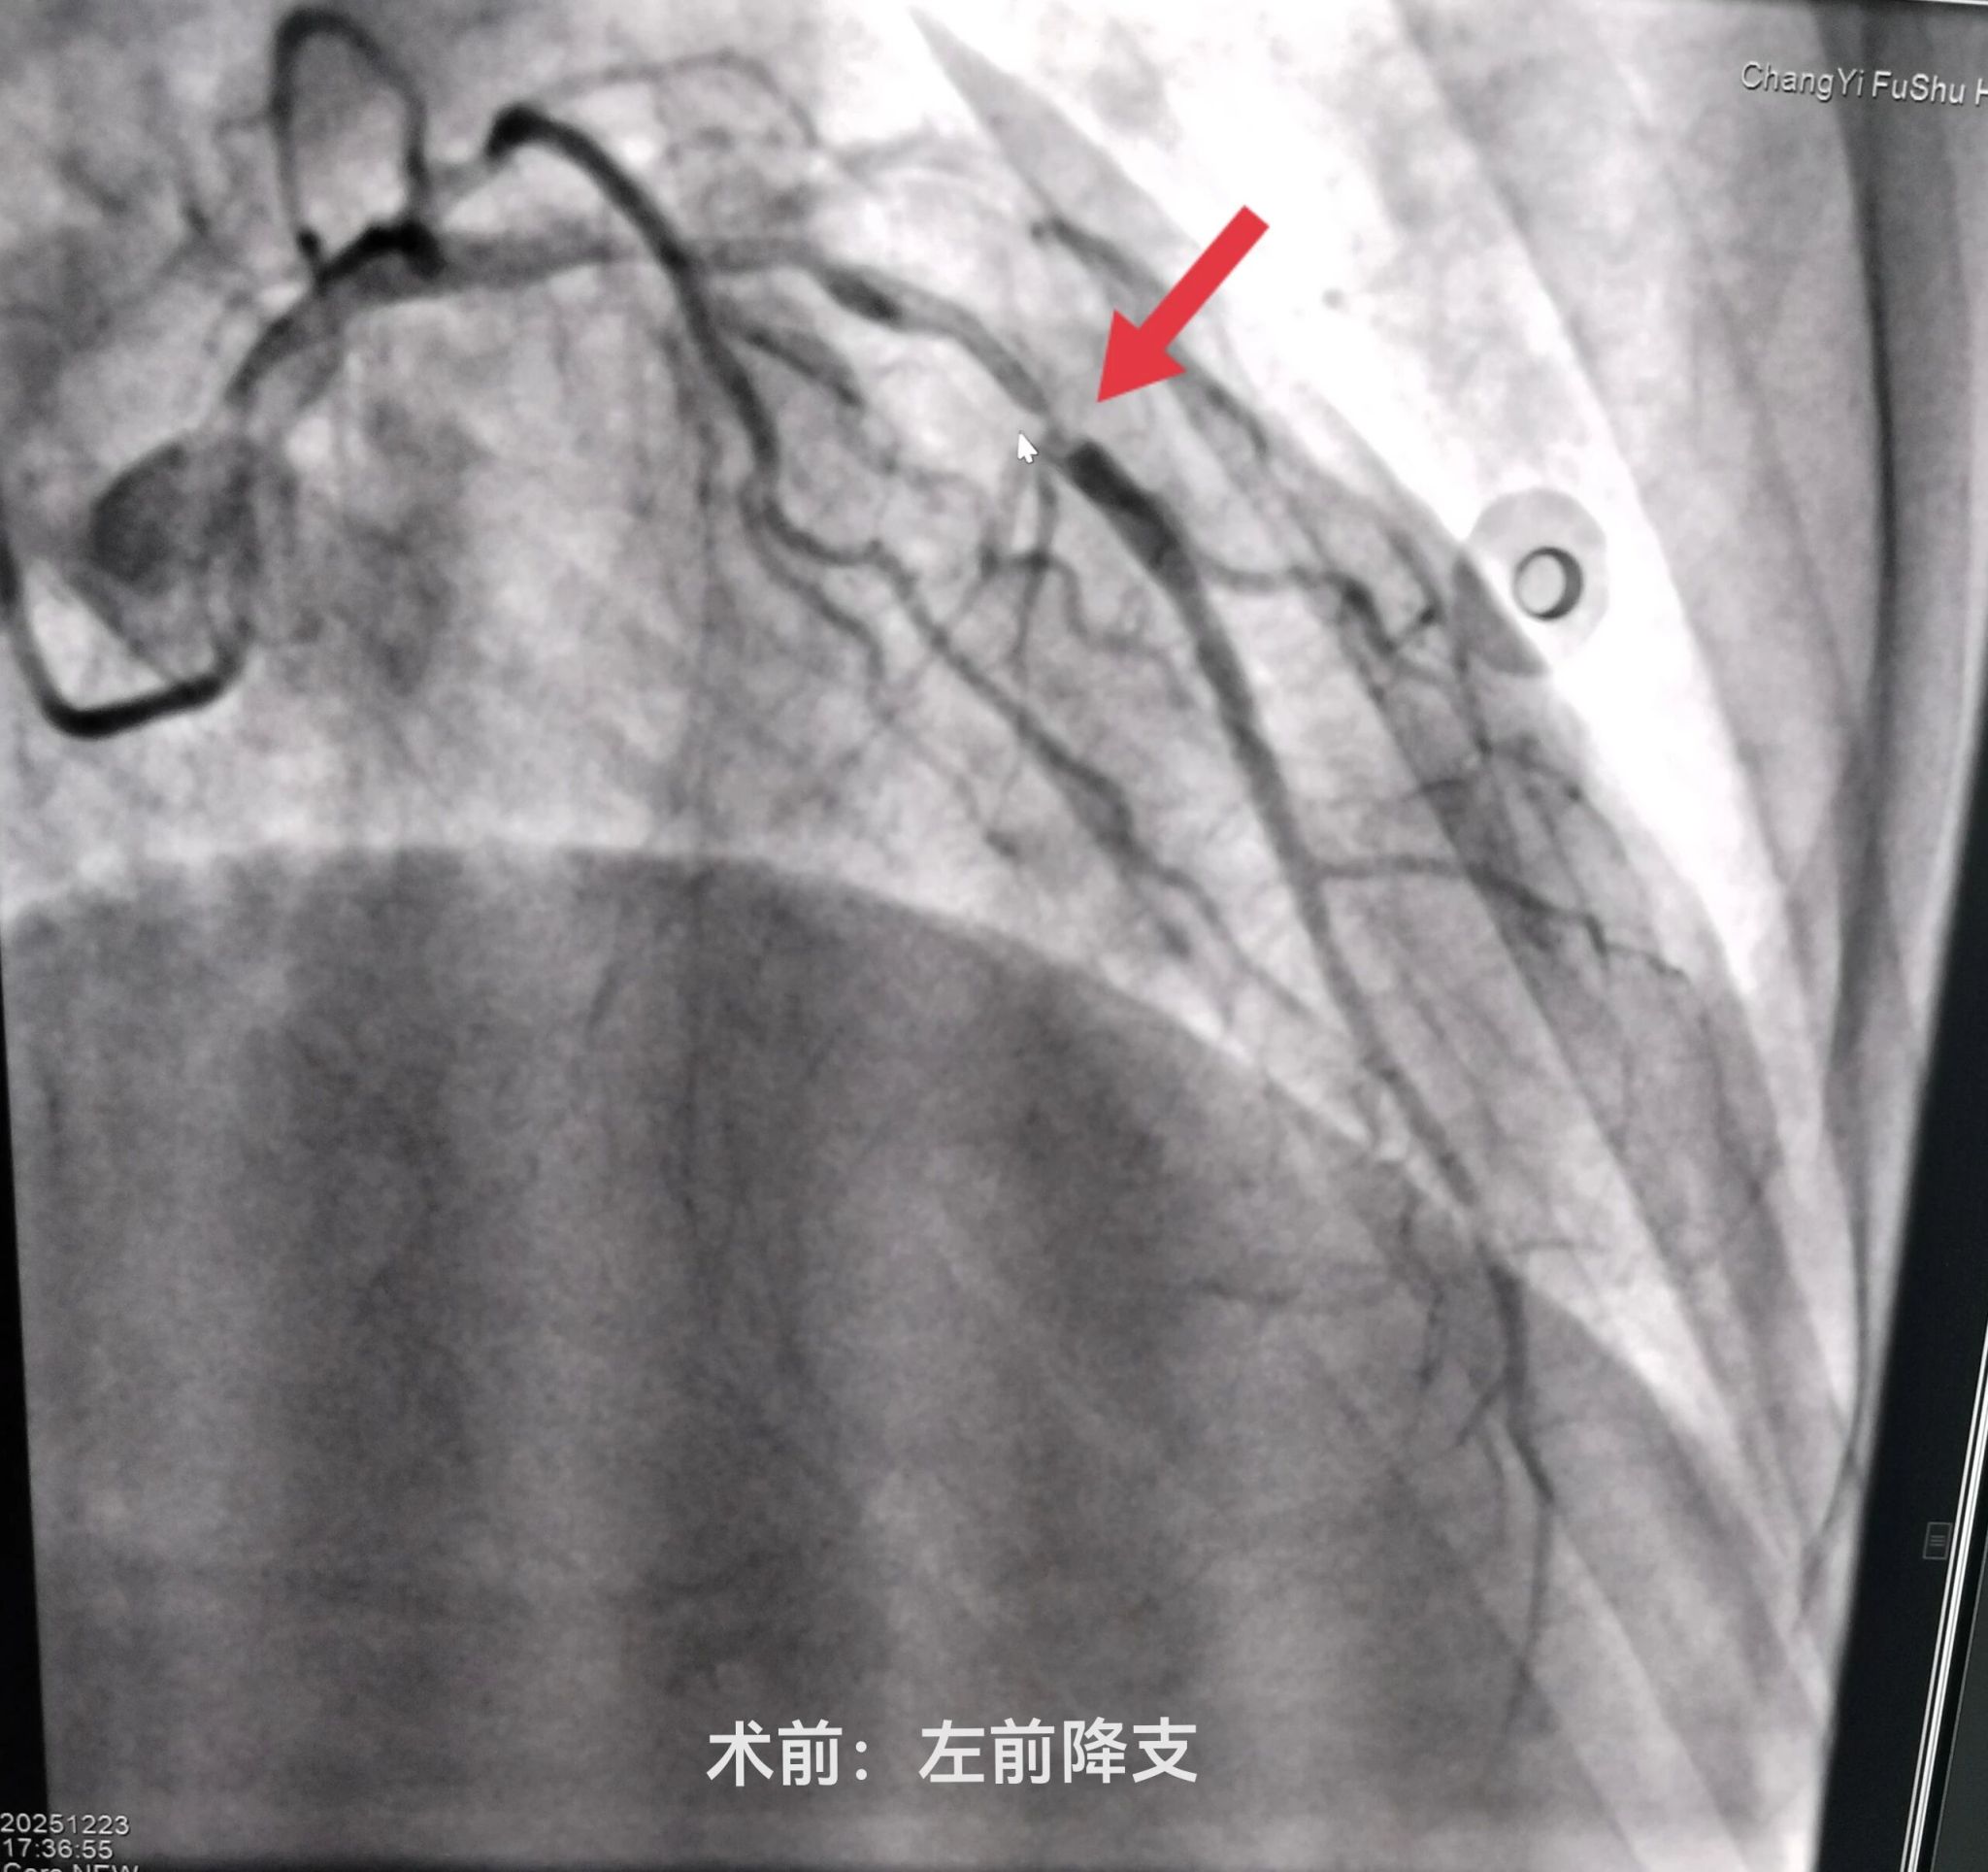

介入室内,医护团队严格遵循标准化操作流程,消毒、穿刺、造影等步骤一气呵成。冠状动脉造影显示心脏三支血管均有严重狭窄,其中两根主要血管均有95%以上的堵塞,患者已出现心力衰竭表现,生命危在旦夕,只有一次性处理两处严重狭窄病变才能为患者带来生的希望。刘晓建主任带领的介入团队凭借丰富的临床经验和精湛的介入技术预判手术风险,勇担重任,术中认真仔细操作,快速高效的同时完成了左前降支(LAD)、右冠状动脉(RCA)球囊扩张及支架植入术。随着支架成功释放,闭塞的血管瞬间恢复通畅,心肌供血得以重建,患者胸闷、胸痛症状较前明显缓解,生命体征逐渐平稳。

术前术后对比